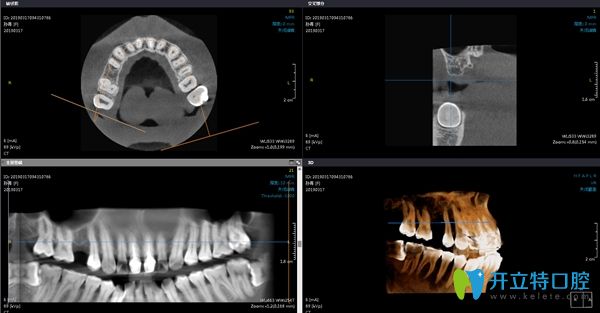

在術(shù)前進(jìn)行常規(guī)的檢查,拍片對(duì)骨質(zhì)量進(jìn)行測(cè)量及評(píng)估,確定擬植入種植體的規(guī)格。

在陽(yáng)光樹(shù)口腔拍牙齒片子